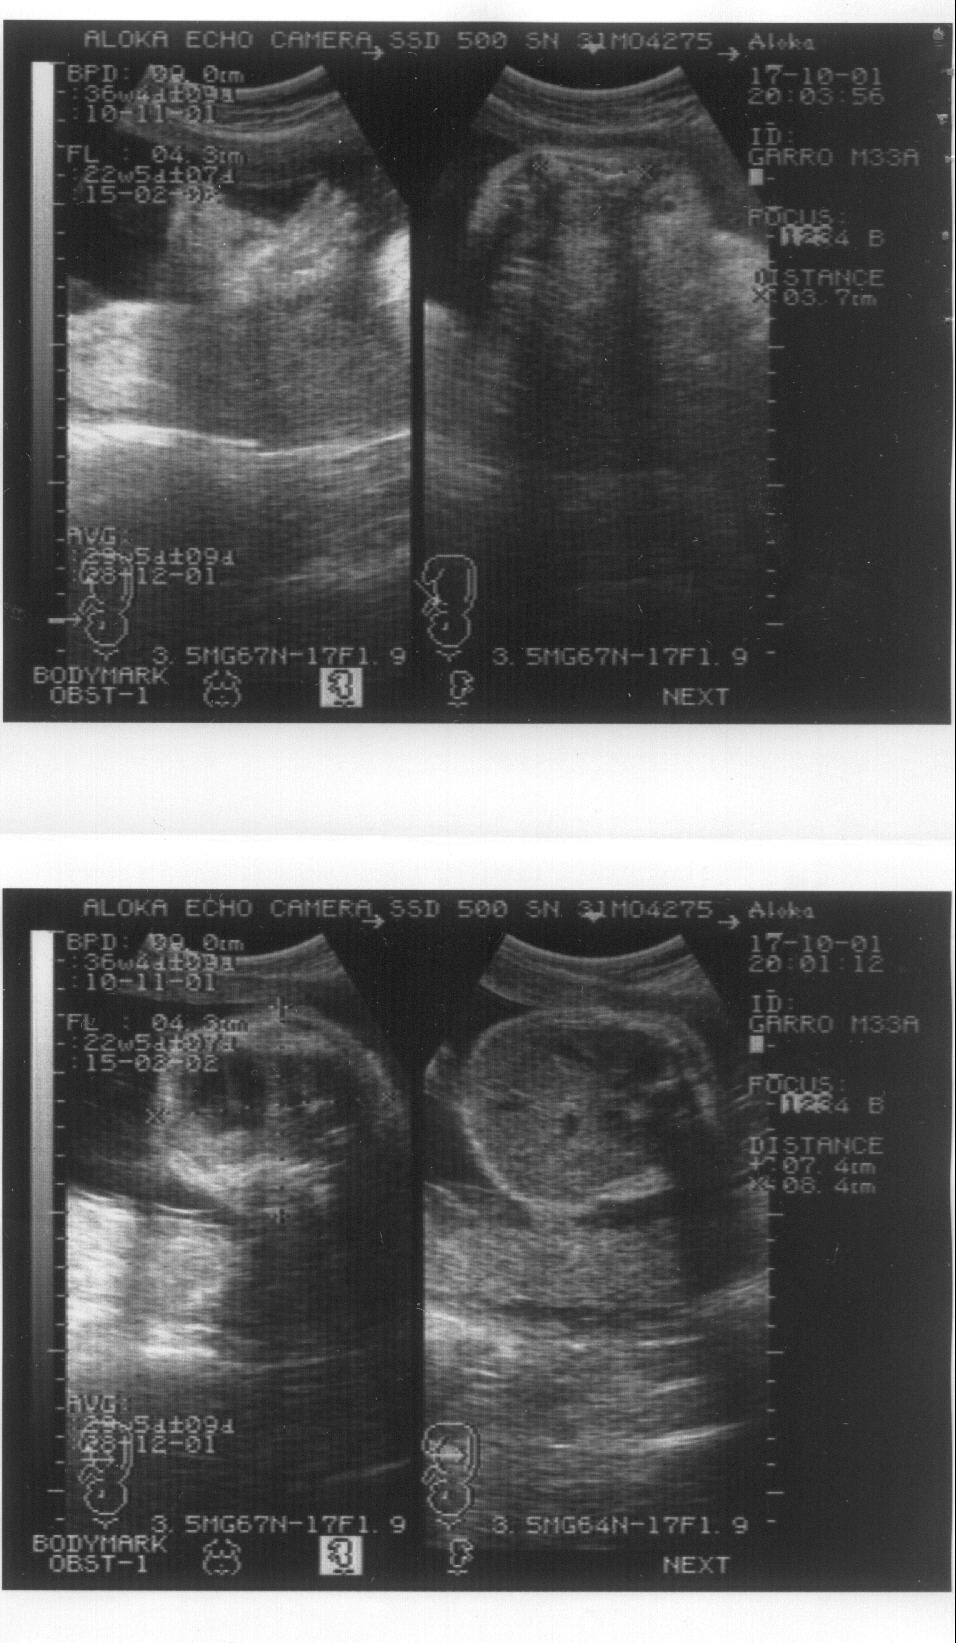

Un caso de osteogénesis imperfecta letal. Octavo mes de embarazo. Imagen 3/4

Imagen de la ecografía